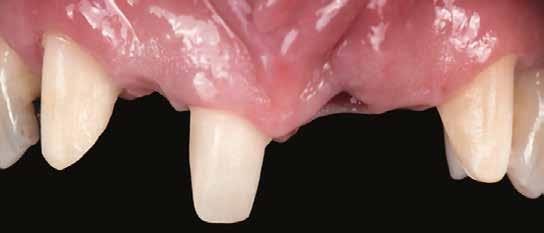

1. a–d. ábrák: Kiindulási klinikai állapot a két páciens esetében: Az első páciensnél a jobb felső premolárisok és az első moláris, a második páciensnél a bal felső második premoláris.

heléssel vagy anélkül). Az első páciensnél gyökérreszorpció miatt szükségessé vált a jobb felső premolárisok és az első moláris eltávolítása (1. a–b ábrák). A második páciensnél a bal felső második premoláris frakturát szenvedett (1. c–d ábrák) Az átfogó tervezést és diagnosztikát CBCT-felvétel segítségével végeztük (2. a–c ábrák), a posztoperatív kontroll és az utánkövetés időszakában pedig periapikális röntgenfelvételeket készítettünk. A jelen tanulmányban résztvevő valamennyi páciens nemdohányzó volt, jó, vagy gyógyszeresen jól karbantartott általános egészségi állapotnak örvendett. A hatékony plakk-kontroll ellenére műtét előtt mindkét páciensnél végeztünk supragingivális depurálást és gyökérsimítást.